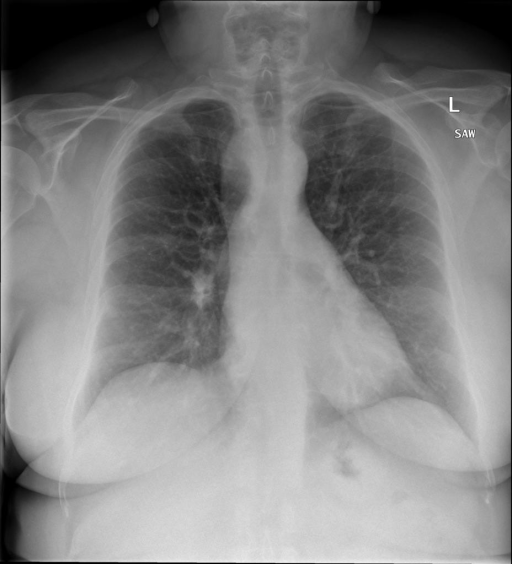

|X光影像|诊疗报告(医生)|XrayGLM|

||X光图片显示没有扭曲的区域、可疑的骨质不透明度或胸腺积液。心脏大小轻微增大,但非常稳定。此外,没有气胸的证据,肺野也正常。总体来说,X光片显示没有急性心脏异常,但要注意轻微的心脏扩大。|X光片显示,心脏大小正常。肺部和纵隔轮廓清晰,没有气胸或胸腔积液的证据。骨骼结构完整,没有任何急性异常。|